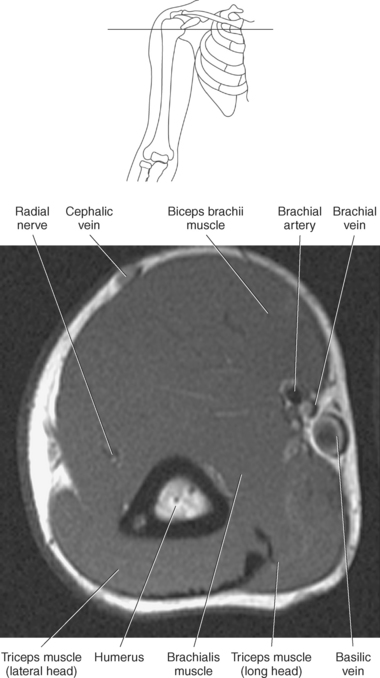

The muscles of the upper arm can be divided into ventral and dorsal groups according to their position. The ventral group contains the biceps brachii, brachialis, and coracobrachialis muscle, and the dorsal group consists of the triceps brachii and anconeus muscles. These muscles are demonstrated in Figures 9.55 through 9.69 and described in Table 9.4.

The biceps brachii muscle is located on the anterior surface of the humerus and acts as a strong flexor of the forearm. The biceps brachii muscle is so named “biceps” because of its two expanded heads of proximal attachment (long and short). The tendon of the long head arises from the supraglenoid tubercle and courses through the intertubercular (bicipital) groove to merge with the tendon from the short head. The short head of the biceps brachii muscle originates from the coracoid process and joins with the long head to create the biceps brachii muscle, which terminates in two tendons. The stronger tendon inserts on the radial tuberosity, and the other tendon creates the bicipital aponeurosis, which radiates into the fascia of the forearm (Figure 9.55).

The brachialis muscle originates from the anterior surface of the distal humerus and covers the anterior surface of the elbow joint before inserting on a roughened area of the proximal and anterior surface of the ulna termed the ulnar tuberosity and the coronoid process. The brachialis muscle is considered to be the most important flexor muscle of the elbow joint (Figure 9.56). The coracobrachialis is a long, narrow muscle located in the superomedial aspect of the arm. It arises from the coracoid process along with the short head of the biceps brachii and extends to insert on the medial surface of the humerus. The primary action of the coracobrachialis muscle is to assist with flexion and adduction of the arm, but it also helps hold the head of the humerus within the joint capsule (Figures 9.56 through 9.67).

The triceps brachii muscle is located on the posterior surface of the humerus and is the main extensor of the forearm. Its name triceps is associated with three heads of proximal attachment (long, lateral, and medial). The long head of the triceps originates from the infraglenoid tubercle of the scapula, the medial head originates from the entire dorsal surface of the humerus distal to the radial groove, and the lateral head arises from the dorsal surface and lateral intermuscular septum of the humerus. All three heads join in a common tendon that inserts on the olecranon process of the ulna and the posterior joint capsule (Figure 9.68). The small, triangular anconeus muscle originates on the lateral epicondyle and crosses obliquely to insert on the dorsal surface of the olecranon process, close to the tendon of the triceps brachii (Figure 9.69). It assists the triceps brachii in extension and also provides dynamic joint stability to the lateral joint capsule. For images of the upper arm, see Figures 9.57 through 9.67.

The primary arteries supplying the shoulder region include the axillary and brachial arteries (Figures 9.34 through 9.45 and 9.144, A). The axillary artery begins at the lateral border of the first rib as a continuation of the subclavian artery. It ends at the inferior border of the teres major muscle, where it passes into the arm and becomes the brachial artery. The axillary artery and its branches supply blood to numerous thoracic and shoulder structures, including the first and second intercostal spaces, axillary lymph nodes, mammary gland in women, and scapular, serratus anterior, pectoral, latissimus dorsi, deltoid, and triceps brachii muscles. The branches of the axillary artery typically include the superior thoracic, thoracoacromial, lateral thoracic, subscapular artery, and anterior and posterior humeral circumflex arteries. The brachial artery is the principal arterial supply to the arm. It courses inferiorly on the medial side of the humerus then continues anterior to the cubital fossa of the elbow. The brachial artery is relatively superficial and palpable throughout its course. It accompanies the median nerve, which crosses anterior to the artery in the middle of the arm. During its course, the brachial artery gives rise to numerous muscular branches, which include the profunda brachii, superior ulnar collateral, and inferior ulnar collateral arteries (Figure 9.144, A).

The veins of the upper arm include the brachial, cephalic, and basilic (Figure 9.146). The two deep brachial veins ascend the arm, one on either side of the brachial artery. The brachial veins begin in the elbow from the union of the ulnar and radial veins and end in the axillary vein near the lower margin of the subscapularis muscle. The two deep brachial veins may join to form one brachial vein during part of their course. The superficial veins of the upper arm include the cephalic and basilic. The cephalic vein courses from the radial side of the dorsal venous arch of the hand and then ascends to the midpoint of the forearm, where it curves around to the ventral surface of the forearm and ascends the lateral aspect of the upper arm, along the anterolateral border of the biceps brachii muscle, to open into the axillary vein, just below the clavicle. It drains the superficial parts of the lateral hand and lateral forearm. The basilic vein originates from the medial end of the dorsal venous arch of the hand. It then ascends the ulnar side of the forearm, along the medial surface of the biceps brachii muscle, in the upper arm, to form the axillary vein. The basilic vein drains the superficial parts of the medial side of the hand and medial side of the forearm. The large axillary vein lies on the medial side of the axillary artery. It extends from the lower border of the teres major muscle to the lateral surface of the first rib to continue as the subclavian vein. The axillary vein receives tributaries that correspond to the branches of the axillary artery (Figures 9.34 through 9.47).